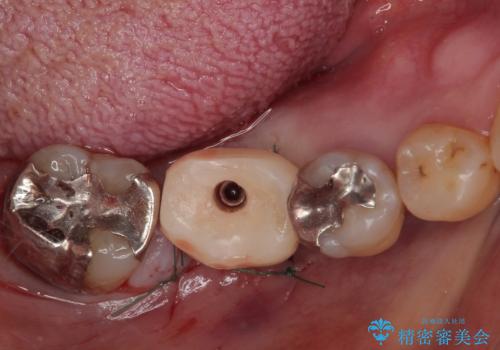

- 奥歯を抜歯してから放置しているとのことで来院された患者様です。

歯が割れて抜歯になってしまったとのことで、咬合力に抵抗できるよう、インプラントによる補綴治療を行うこととしました。

むし歯の放置期間と抜歯してからの放置期間が長く、咬み合わせる上顎の歯がやや伸び出している状態でした。

上顎の部分矯正や対合歯の補綴治療も提案しましたが、今回は欠損部のみの治療を行いました。